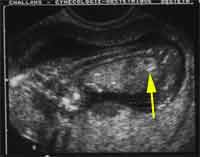

14 semaines